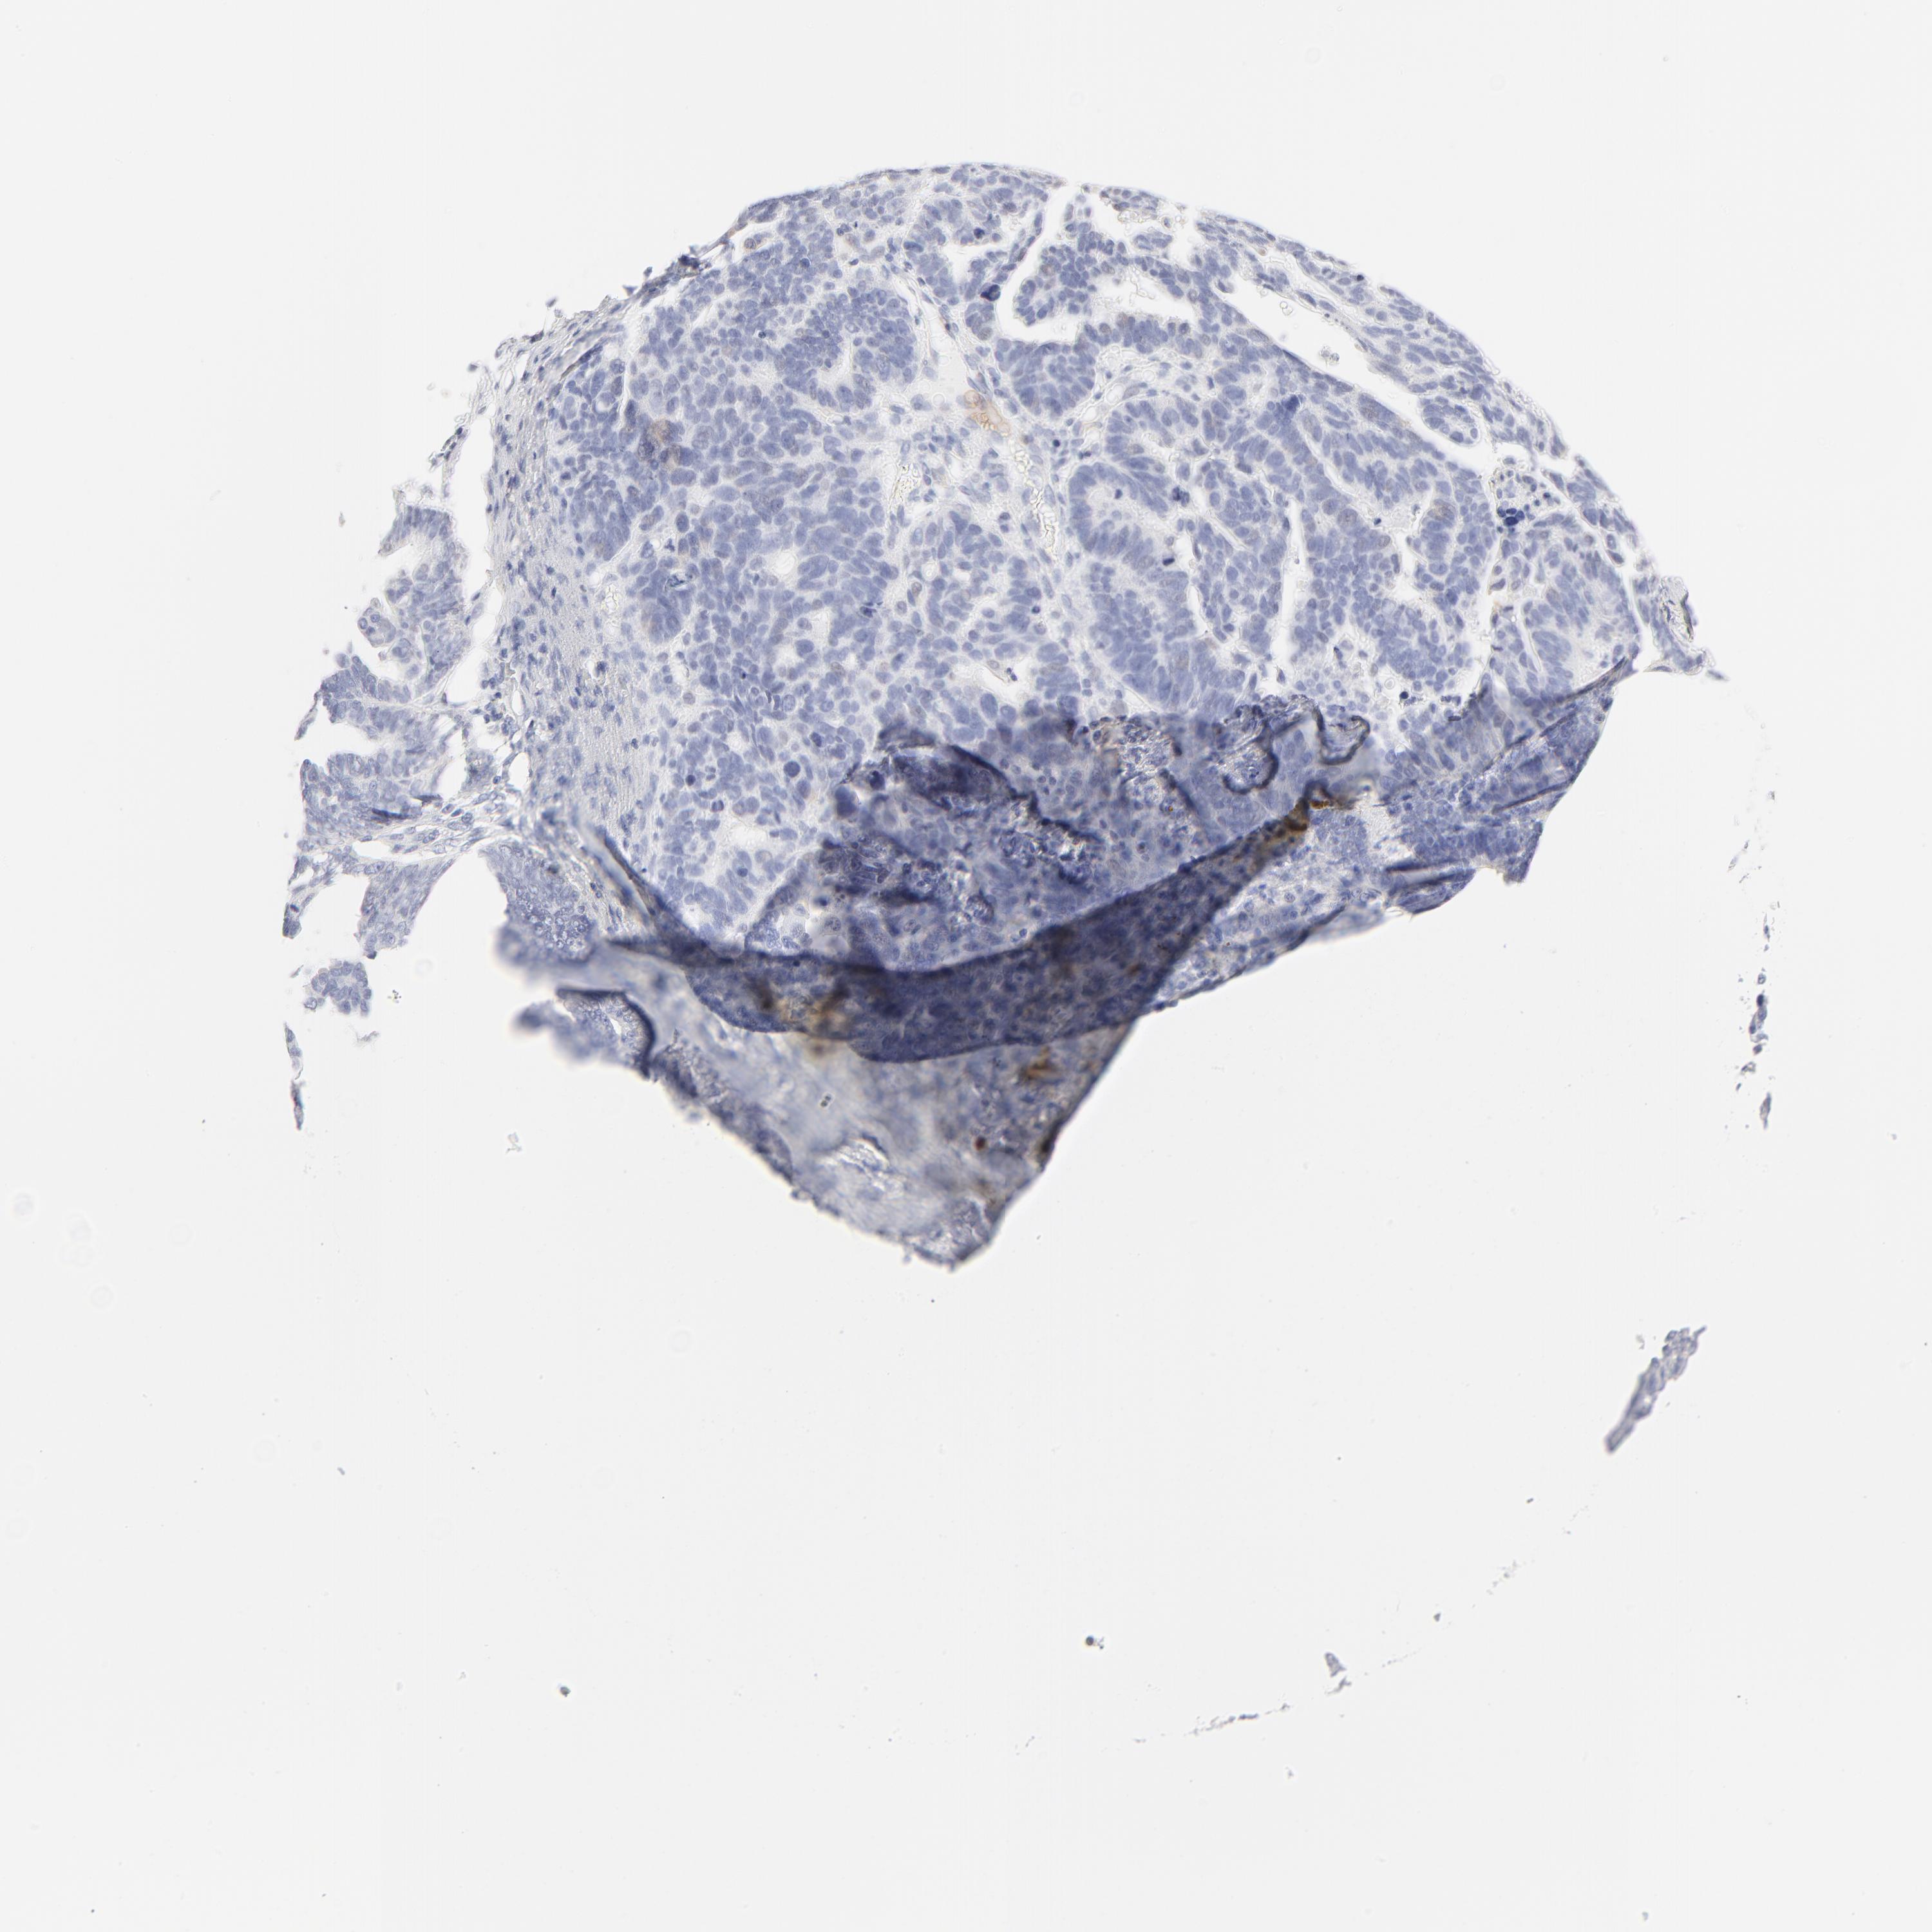

OVARIAN CANCER - Protein expressioni

A mouse-over function shows sample information and annotation data. Click on an image to view it in a full screen mode. Samples can be filtered based on level of antibody staining by selecting one or several of the following categories: high, medium, low and not detected. The assay and annotation is described here.

Note that samples used for immunohistochemistry by the Human Protein Atlas do not correspond to samples in the TCGA dataset.

Antibody stainingi

Antibody staining in the annotated cell types in the current human tissue is reported as not detected, low, medium, or high, based on conventional immunohistochemistry profiling in selected tissues. This score is based on the combination of the staining intensity and fraction of stained cells.

Each image is clickable and will lead to virtual microscopy that enables deeper exploration of all samples and also displays staining intensity scores, fraction scores and subcellular localization as well as patient and tissue information for each sample.

Antibody HPA003371

Staining

High

Medium

Low

Not detected

Intensity

Strong

Moderate

Weak

Negative

Quantity

>75%

75%-25%

<25%

None

Location

Nuclear

Cytoplasmic/membranous

Cytoplasmic/membranous,nuclear

Cystadenocarcinoma, mucinous, NOS

Carcinoma, endometroid

Cystadenocarcinoma, serous, NOS